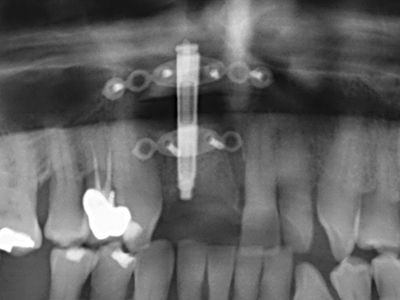

Фиг. 17a: CT изображение на стимулиращата растеж остеотомия в непосредствена близост до...

Фиг. 17b: алвеоларния канал с нервни окончания (латерален и коронарен изглед).

Фиг. 18: Препарация на кортикално покритие с пиезо накрайник за кост (Piezomed, W&H).

Фиг. 19: Хирургичното поле след невролиза и отстраняване на остеотом.

Фиг. 20: Отстраненото костно покритие е поставен отново и фиксиран с винт за остеосинтеза (KLS Martin, Tuttlingen).

Фиг. 21: Разширена челюст с дефект на преден зъб с индикация за остеогенеза с белези от предходна операция.

Фиг. 22: Подвижният сегмент може да бъде прецизно отделен с тънкия трион за остеотомия (W&H Piezomed).

Фиг. 23: Финално преместване на палатинално отделения сегмент с длетото.

Фиг. 24: Приложение на разделичителя (TRACK-System, KLS Martin).

Фиг. 25: Панорамна снимка след достигане на финалната височина на раздалечаване, преди периода на консолидиране.

Фиг. 26: Стабилни условия преди поставяне на импланта и след периода на консолидиране от 4 месеца.